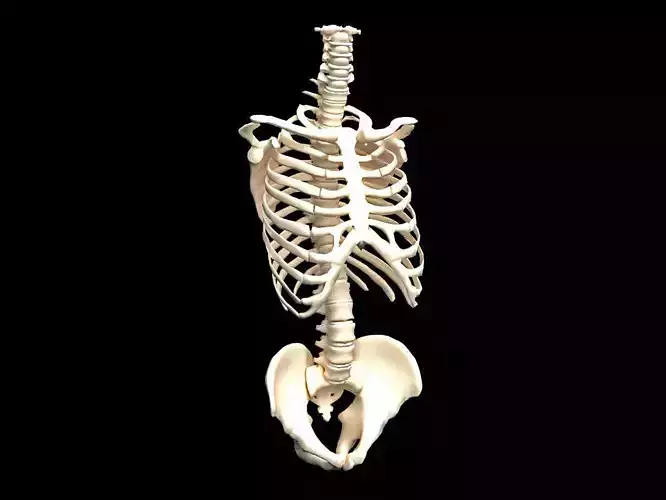

Model is not 3D printable

The designer indicates this model is intended for digital use only (rendering, animation, or AR/VR) and not for 3D printing.